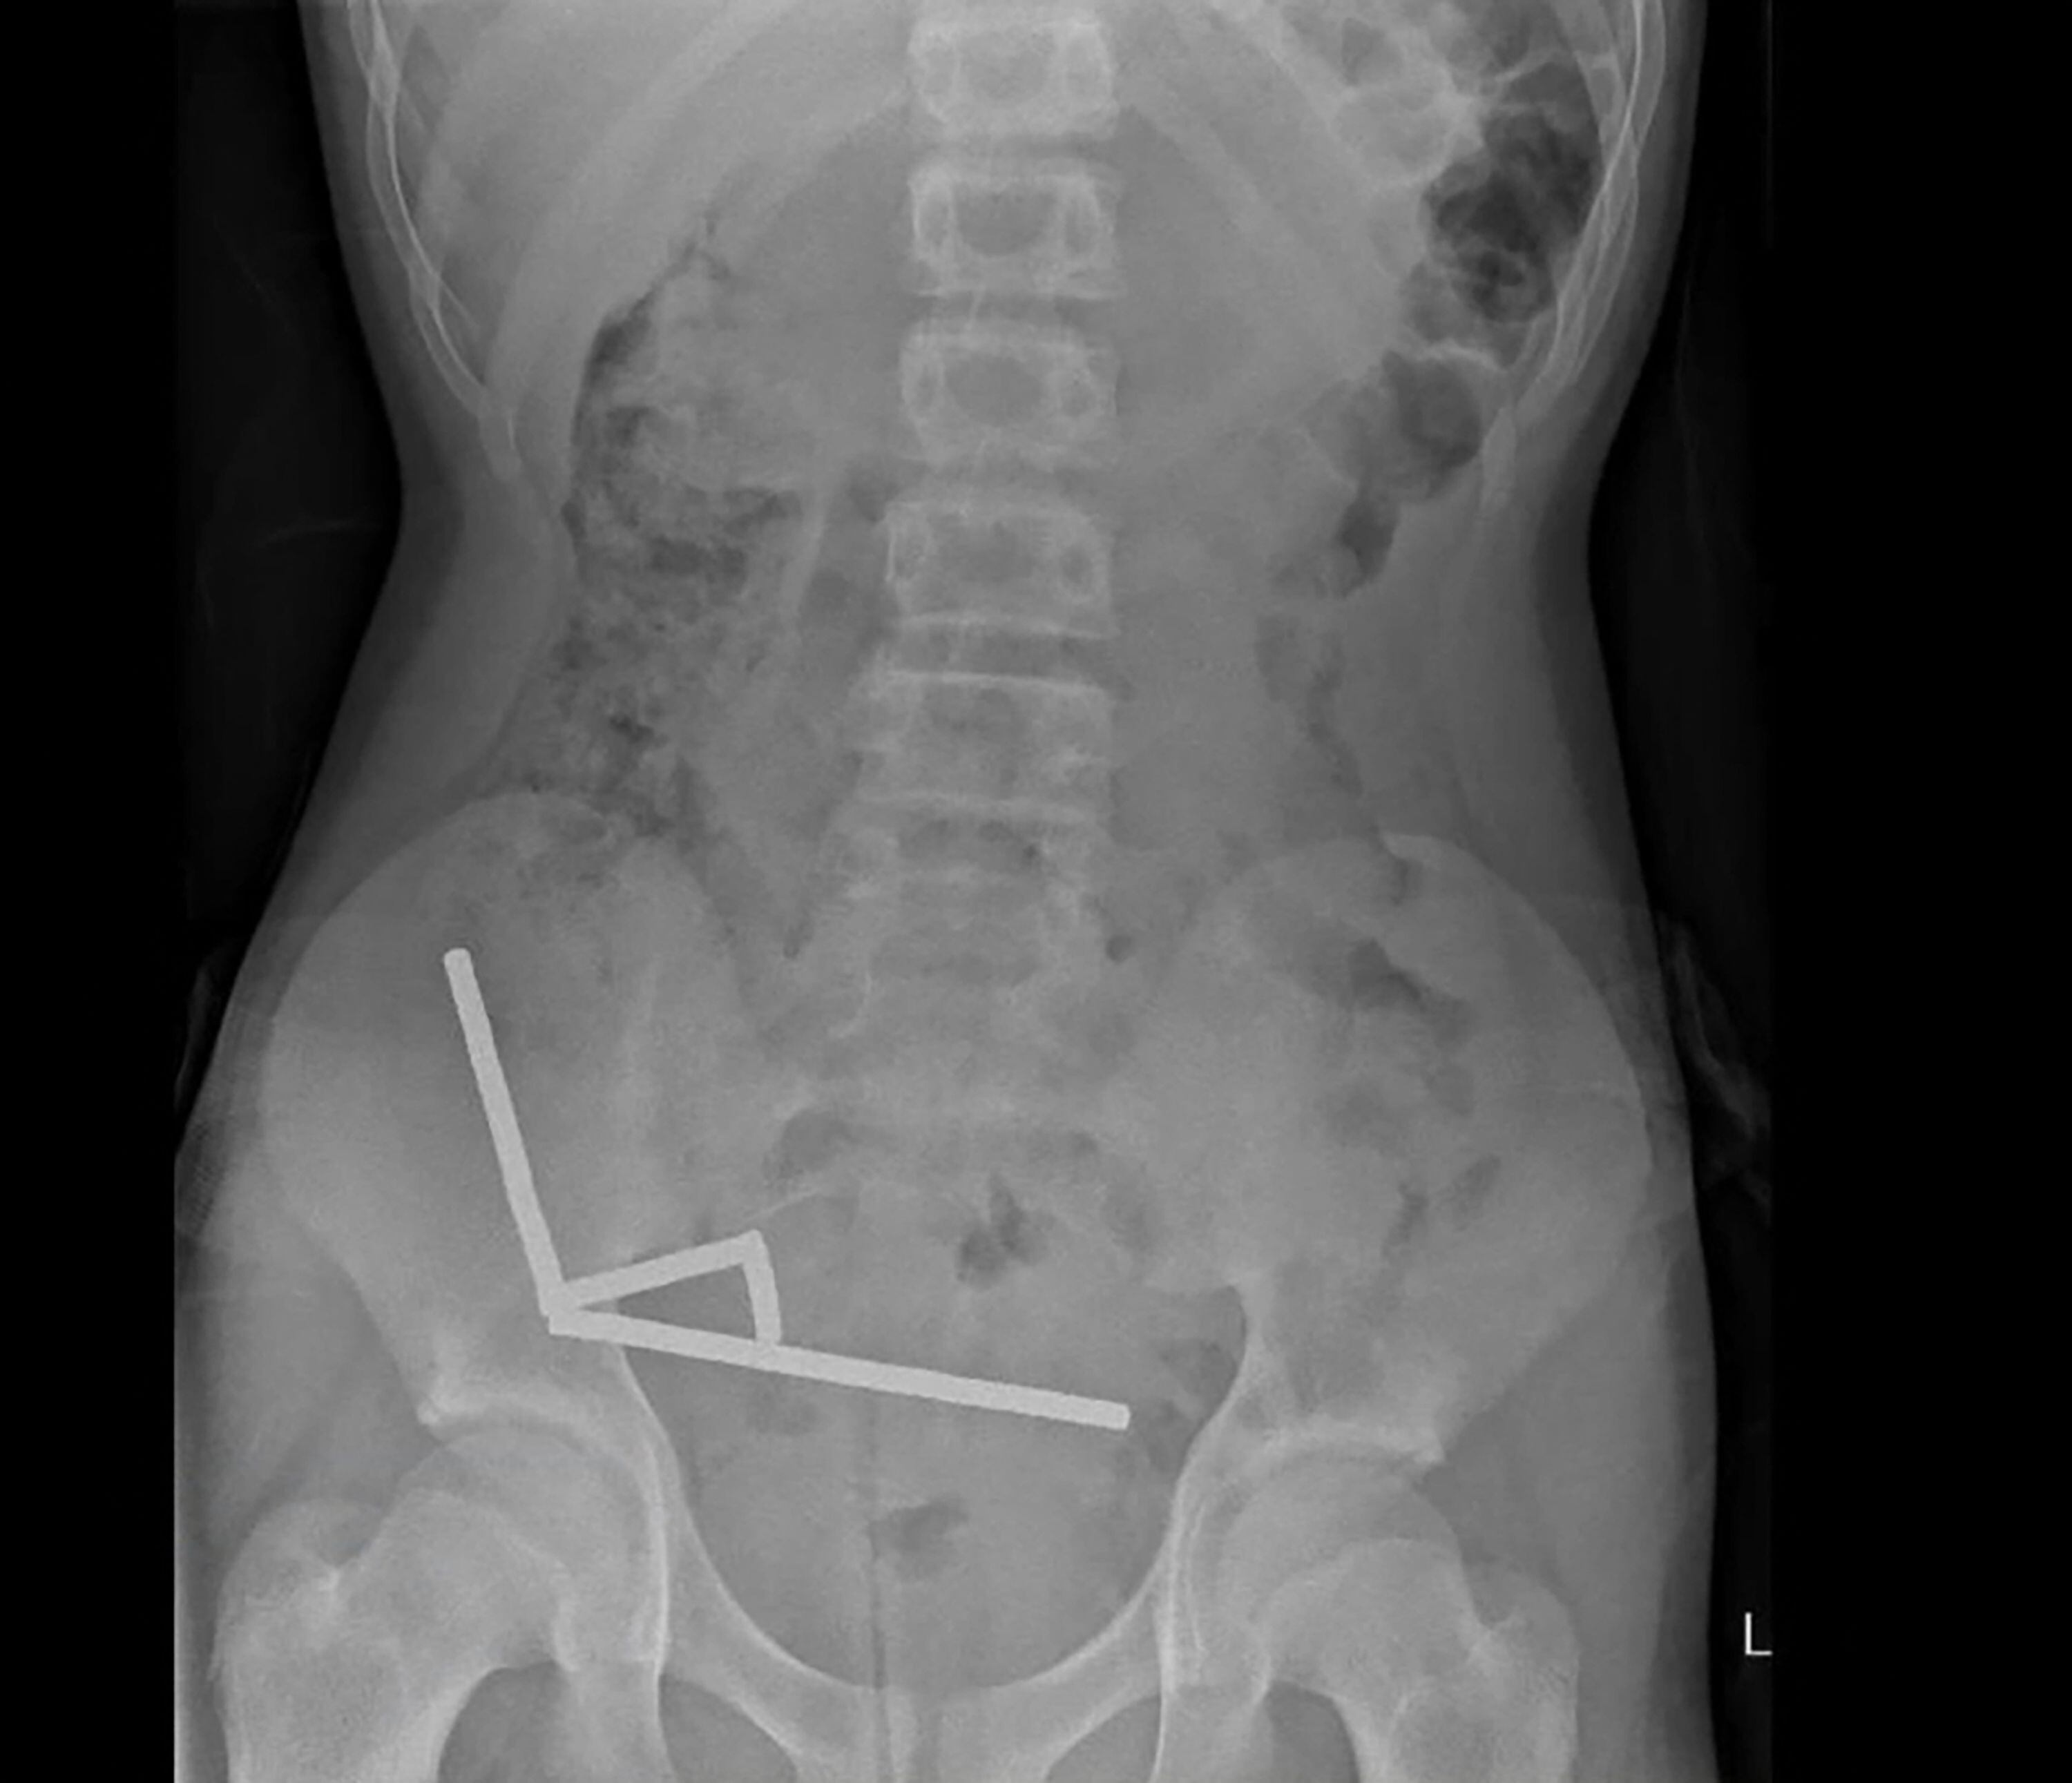

Exames revelaram que os ímãs se agruparam em quatro cadeias na parte inferior direita de seu abdômen, unindo diferentes seções de seu intestino com sua força magnética, disse o relatório, observando que algumas imagens foram distorcidas pelos ímãs. Os médicos, então, prosseguiram com cirurgia exploratória.